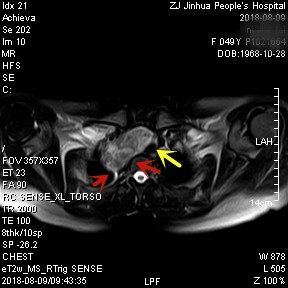

上图均示MRI下的肿瘤情况,红色箭头示肿块

上图示颈部与胸内的病灶关系密切,但绿色箭头处似有分界,仅少许相连